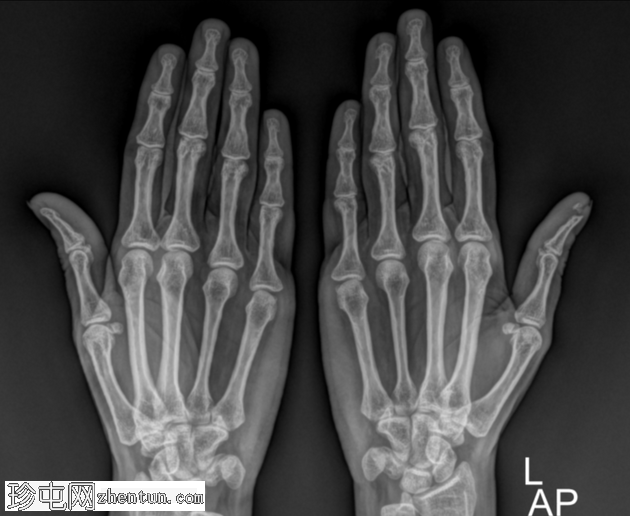

左手拇指外伤。

年龄:50岁

性别:女

X光片

斜位

拇指远端指骨末端(指骨束)轻度移位骨折。

拇指远端指骨末端指骨束骨折移位。